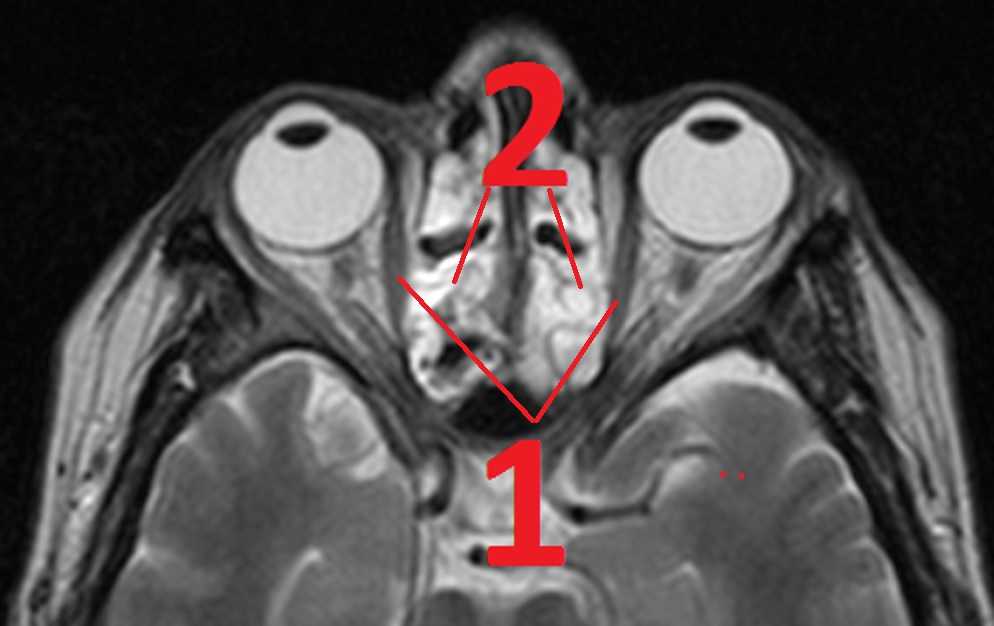

МР-томограмма. Боль в глазных яблоках и голове, распирание, жжение и зуд в глазах, экзофтальм, двоение при движении глаз, боль в висках и глазах.

Причина – воспаление в пазухах носа.1 – воспаленные утолщенные (отёчные) мышцы глаз2 – источник боли в глазах – полипы и гной в пазухах носа (на МРТ – белого цвета)